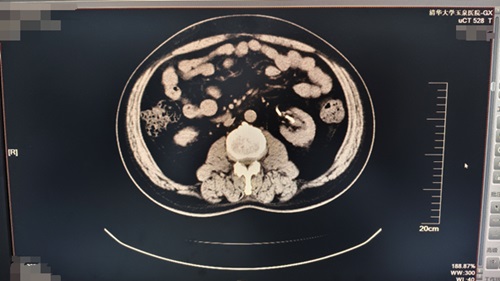

术后6周复查泌尿系CT,左输尿管内支架置入术后,左肾结石基本消失。

术后6周复查泌尿系CT,左输尿管内支架置入术后,左肾结石基本消失